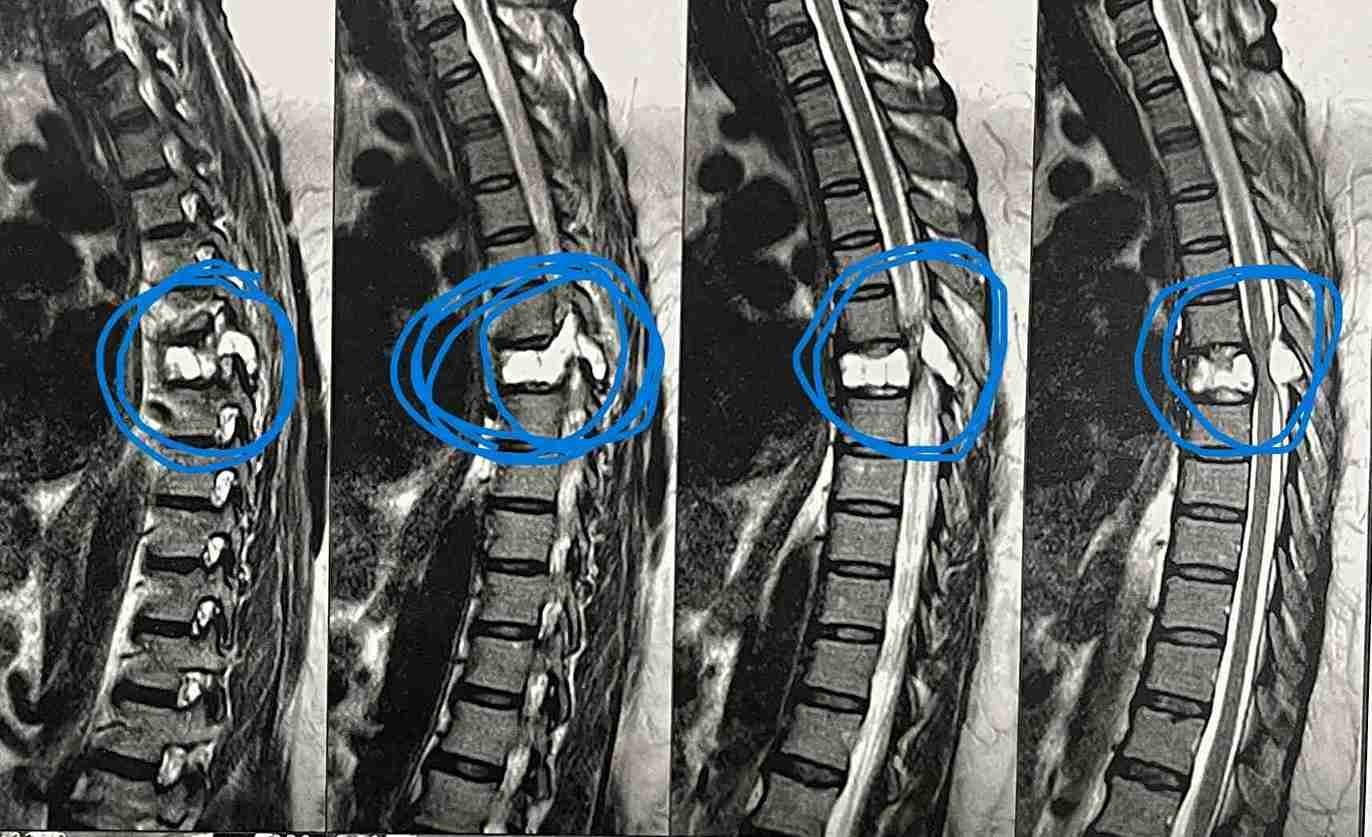

مريضة عمرها 43 عام تعاني من ضعف متزايد بالطرفين السفليين.

43-year-old female patient suffers from increasing weakness in the lower extremities

A 43-year-old woman suffering from progressive weakness in both lower limbs was diagnosed and treated. This condition affects walking ability and mobility, requiring thorough neurological evaluation to determine the underlying cause and develop an appropriate treatment plan.